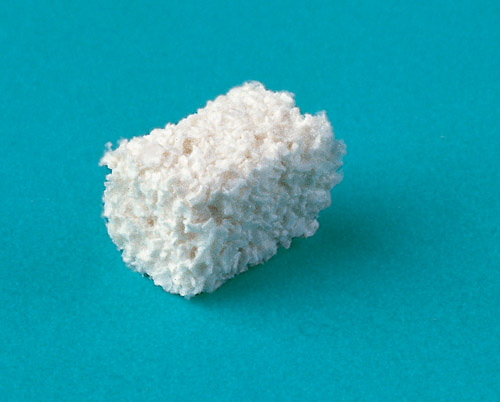

— графты (иначе говоря, спейсеры, остеокондукторы), т. н. «заменители костной ткани»:

Начну, пожалуй, с того, что принципиальной отличий в механизме действия различных графтов нет. Всё, начиная с ксенотрансплантатов и, заканчивая синтетикой, работает по одним и тем же принципам. В нашей клинике мы используем биоматериалы разных производителей, а их применение рассматривается, почти исключительно, с точки зрения удобства. Так, для лунок зубов, для аугментации при немедленной имплантации, мы используем Bio-Oss Collagen (Geistlich):

На сегодняшний момент не существует графтов, улучшающих структуру костной ткани или её качество, стимулирующих остеогенез или ускоряющих регенерацию. Несмотря на то, что они могут существенно отличаться по своим физическим и биологическим свойствам, их назначение всегда одно:

заполнить и удержать объем, необходимый для регенерации костной ткани, создать, своего рода, матрицу, способную удержать в себе мигрирующие клетки.

И, учитывая то, что аутокостная стружка довольно быстро и сильно резорбируется (до 50-70% по данным некоторых авторов), медленно рассасывающийся ксенографт способен, хоть и не полностью, сохранить запланированную форму альвеолярного гребня.

Зная понятие периметра, мы с предсказуемо хорошим результатом можем регулировать слой графта в т. н. «пределах роста» костной ткани, т. е. расстояния, на которое способны двигаться клетки и расти сосуды.

В последнем предложении, по сути, раскрыт главный секрет применения графтов. Безусловно, эта тема еще требует специальных исследований и наблюдений, однако соблюдение этого простого правила (например, не больше 2-3 мм от периметра костного дефекта) позволит избежать многих проблем и осложнений в имплантологической практике.